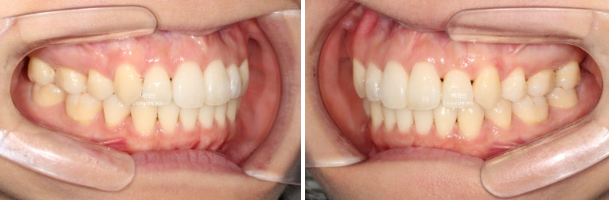

23.01

앞니 덧니가 보입니다.

중심선이 약 2mm 어긋나 있습니다.

앞니 뻗침은 심한 편 입니다.

인비절라인을 원하셔서 인비절라인 발치교정을 권유드렸습니다.

작은어금니 4개를 발치하기로 했습니다.

첫번째 세트의 장치는 총 80개가 나왔습니다.

일주일에 한 개씩 장치를 교체하며 진행했습니다.